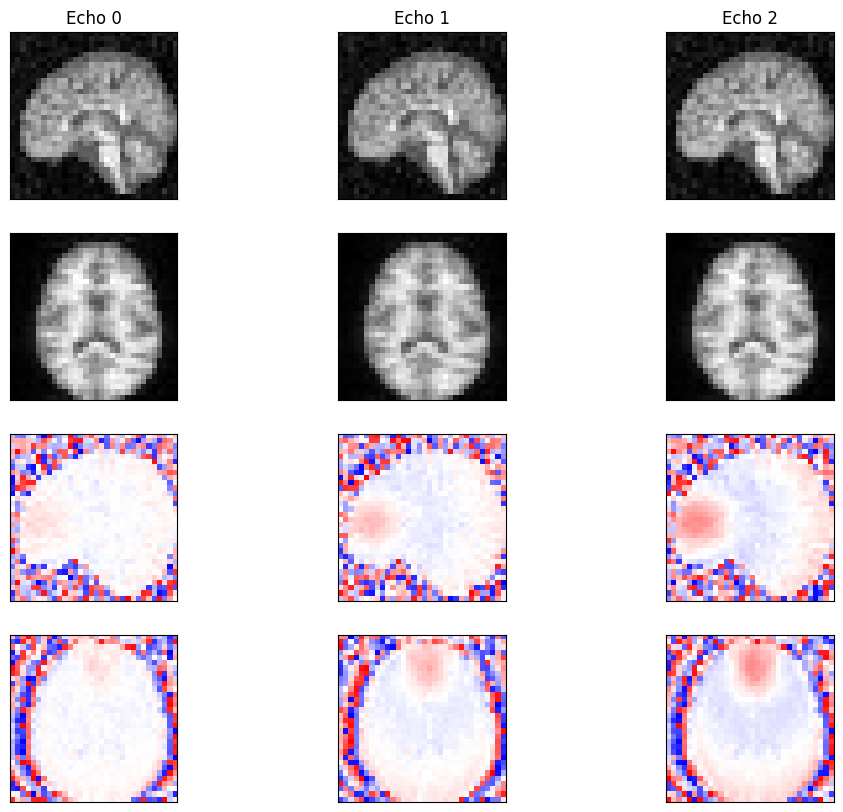

Compare to Theoretical Model#

Compare the reconstructed images to a theoretical spoiled GRE signal model. We calculate \(T2^*\) using \(1/T2^* = 1/T2 + 1/T2'\).

fig, ax = plt.subplots(3, 3, figsize=(12, 10))

x_mid = idat.shape[-1] // 2

for echo in range(3):

im = ax[0, echo].imshow(idat[echo, :, :, x_mid], cmap='grey', vmin=0, vmax=1)

ax[0, echo].set_title(f'Echo {echo} - Reconstructed')

ax[0, echo].set_xticks([])

ax[0, echo].set_yticks([])

fig.colorbar(im, ax=ax[0, echo])

im = ax[1, echo].imshow(idat_model[echo, :, :, x_mid], cmap='grey', vmin=0, vmax=1)

ax[1, echo].set_title(f'Echo {echo} - Model')

ax[1, echo].set_xticks([])

ax[1, echo].set_yticks([])

fig.colorbar(im, ax=ax[1, echo])

im = ax[2, echo].imshow(idat_diff[echo, :, :, x_mid], cmap='bwr', vmin=-0.2, vmax=0.2)

ax[2, echo].set_title(f'Echo {echo} - Difference')

ax[2, echo].set_xticks([])

ax[2, echo].set_yticks([])

fig.colorbar(im, ax=ax[2, echo])

plt.tight_layout()

plt.show()

relative_error = np.sum(np.abs(idat_diff)) / np.sum(np.abs(idat_model))

print(f'Relative error: {relative_error:.4f}')

assert relative_error < 0.09

_images/48b8cc71e5cd3f9d784da343d180f72543f040b9c54f076cd7e80de6b5ca41ca.png

Relative error: 0.0890